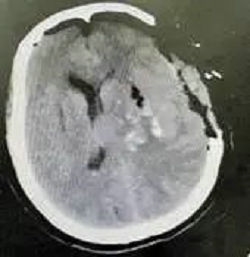

患者女性,64岁,突发意识障碍入院。患者病情危重,随时可能出现脑疝,危及生命。周少龙博士仔细阅读病人CT后认为,该患者左侧丘脑、基底节区出血并破入脑室,血肿量大于30ml,并且双侧瞳孔不等大,手术指征明确,建议急诊行内镜辅助下左侧丘脑、基底节区血肿清除术。

患者术前CT